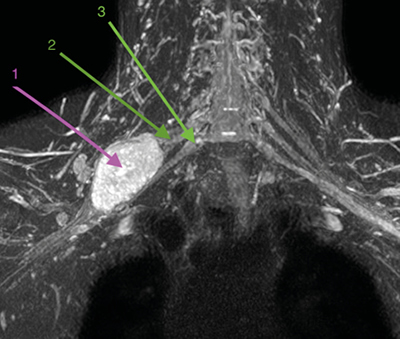

Figura 2